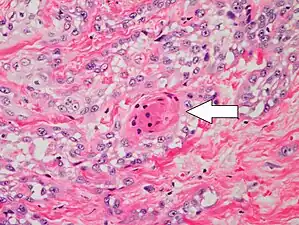

Degree of differentiation

Poorly differentiated, where attempts at keratinization are often no longer evident. This is a clear-cell squamous-cell carcinoma. The dysplastic cells infiltrated cords through the dermis. Poorly differentiated cSCC has greatly enlarged pleomorphic nuclei showing a high degree of atypia and frequent mitoses.[12]

Poorly differentiated clear-cell squamous-cell carcinoma. For this type of cSCC, immunostains will likely be required to classify it unless other areas of the tumor show obvious squamous-cell features such as seen here (arrow).